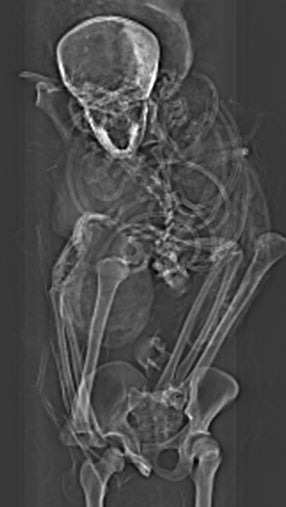

La momia del faraón, que fue descubierta en la década de 1880, fue analizada con rayos X en la década de 1960, mostrando que contenía una serie de graves heridas en la cabeza. Esto dio lugar a todo tipo de especulaciones sobre las circunstancias de su muerte, y dejó a los historiadores preguntándose si murió en el campo de batalla o a a manos de conspiradores asesinos. Tampoco estaba claro por qué Seqenenre, un gran faraón, había sufrido una una momificación tan mala.

En un esfuerzo por responder a estas preguntas, un equipo de arqueólogos dirigido por Sahar Saleem, profesor de radiología en la Universidad de El Cairo, sacó varias tomografías computarizadas para volver a analizar la momia, que se conserva en el Museo Egipcio de El Cairo. El equipo de investigación, que incluía a Zahi Hawass, arqueólogo del Ministerio de Antigüedades de Egipto, también revisó la literatura arqueológica y evaluó cinco armas asiáticas descubiertas previamente en Tell-el-Dabaa. Estas armas, tres dagas, un hacha de guerra y una lanza, se remontan a los tiempos del reinado y la muerte de Seqenenre.

El nuevo análisis mostró que la momia se encontraba en muy mal estado. La cabeza ya no estaba conectada al cuerpo, muchas vértebras y costillas estaban sueltas y quedaban muy pocos tejidos blandos o músculos en los huesos.

La investigación mostró que Seqenenre tenía alrededor de 40 años cuando murió y que medía 1,67 metros de altura.

Encontraron un cerebro encogido y seco en el lado izquierdo del cráneo, y no parece que sus embalsamadores hicieran ningún intento por extraerlo, a diferencia de sus otros órganos. De hecho, no se pudo encontrar evidencia de materiales de embalsamamiento.

Seqenenre no tenía fracturas en el cuerpo, pero su cabeza y su rostro estaban gravemente afectados. La gran fractura de su frente fue atribuida a un “objeto pesado y afilado como una espada o un hacha”, según el documento. La ubicación de la herida sugiere que un asaltante asestó el golpe mortal desde una posición por encima del faraón. Un arma de doble filo, como un hacha de batalla de bronce, probablemente fuese la causante de la “gran fractura” sobre la ceja derecha de Seqenenre, y algún tipo de objeto de fuerza contundente, como el mango de un hacha, fue el responsable de los múltiples golpes sobre la cara del faraón. Una herida penetrante debajo de la oreja izquierda de la momia y en la base de su cráneo probablemente fuese causada por una lanza.

Los investigadores dijeron que cualquiera de estas lesiones habría sido fatal. Las tomografías computarizadas confirmaron que todas las lesiones en el cráneo y la cara fueron infligidas en el momento de la muerte, ya que no hay ninguna evidencia de que hubiese ninguna cicatrización en marcha.